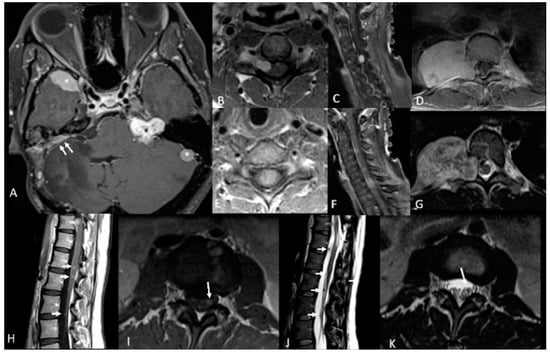

| Vestibular Schwannomas | ~90% | Tinnitus Hearing loss Ataxia | Antoni A, B regions Verocay bodies Hyalinzed vessels | Often bilateral. Slightly T1 hypointense (63%) or isointense (37%). Heterogeneously T2 hyperintense (Antoni A: relatively low, Antoni B: high), cystic degenerative areas may be present if large tumor. Intense contrast enhancement on T1 C+ (Gd) | Radiosurgery Chemotherapy; Bevacizumab | Facial nerve injury Malignant transformation |

| Peripheral Schwannomas -Tumorlets -Plexiform | ~70% | Neuropathic pain Loss of sensation Weakness Tumors on skin, head and neck region (Plexiform) | Antoni A, B regions Verocay bodies Hyalinzed vessels Infiltration of nerve | T1: 75% are isointense, 25% are hypointense. T2: more than 95% are hyperintense, often with mixed signal. Intense contrast enhancement on T1 C+ (Gd) | Intraneural dissection Excision | Rarely undergo malignant transformation although high risk of nerve infiltration |

| Meningiomas | ~50% (20% are in kids) | Headache Seizure | Fibrous morphology Psamomma Bodies High mitotic index | Intense and homogeneous enhancement. Frequent cystic components Can be multiple Present in unusual locations: craniocervical junction. | Surgical excision Radiosurgery Current clinical trial: mTORC1/2 inhibitor AZD2014 (NCT02831257, NCT03071874) | Malignant transformation Invasion to vascular brain structures Compression effect |

| Ependymoma Glial | ~30% | Asymptomatic | Perivascular pseudorosettes Ependymal rosettes | Usually spinal intramedullary (not intracranial/intraventricular). “String of pearls” appearance along the spinal cord and cauda equina. | Monitoring/surveillance Surgical resection if symptomatic | Malignant transformation is rare |